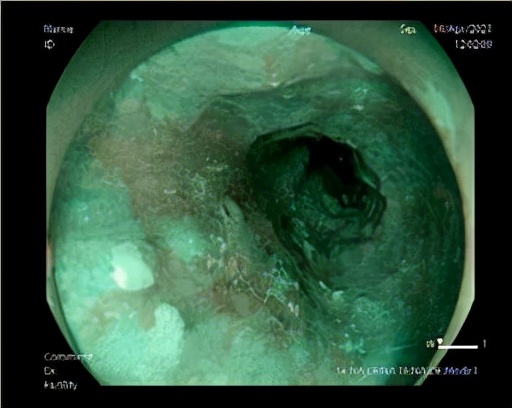

医生询问过后得知:男性,66岁,爱吃腌制食品,有抽烟、饮酒史,进食后胸骨后烧灼感,进食哽咽感,需高度怀疑食道病变,建议患者进行胃镜检查。胃镜提示食管距食道距门齿约38~40 cm处食管见一处表浅平坦型病变,表面色泽发红,黏膜粗糙,边界清晰,碘染色呈大片状不染区。活检病理结果:(食道)少量浅表黏膜,伴局灶高级别上皮内瘤变。医生向H先生交代疾病进展及治疗的必要性,患者住院行内镜下粘膜切除术。

术后病理提示:(食道)原位鳞状细胞癌(3.0*1.8*0.2 cm),未见脉管癌栓及神经侵犯,水平切缘及基底未见癌组织。非常幸运的黄先生其食管早癌治愈了。